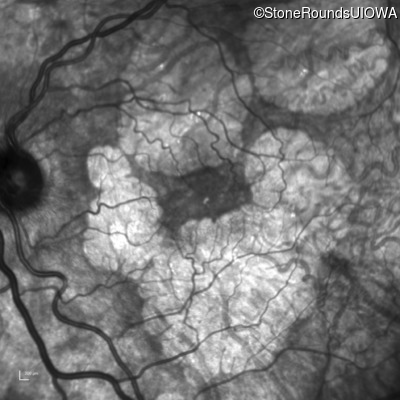

Infrared Fundus Photograph - Right - 20/20 -3

Exemplar